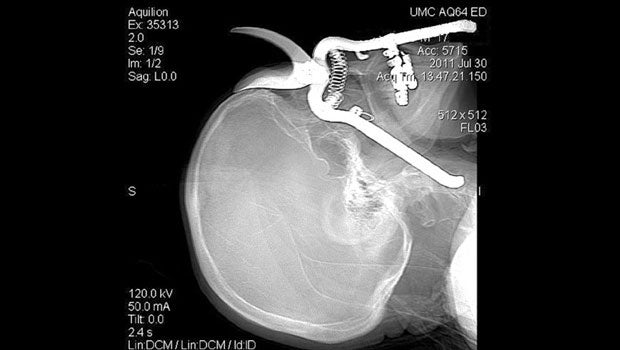

Leroy Luetscher, an 86-year-old Arizona man, is lucky to be alive after accidentally impaling his eye with pruning shears.

Luetscher was working in his yard on July 30, when he dropped the shears - point-side down - then lost his balance while trying to pick them up. The shears penetrated his eye socket and went down into his neck, reaching on carotid artery - the main provider of blood to the brain.

"You wouldn't believe your eyes," his surgeon Dr. Julie Wynne, assistant professor of surgery at University Medical Center in Tucson Arz., said in a written statement. "Half of the pruning shears was sticking out and the other half was in his head."